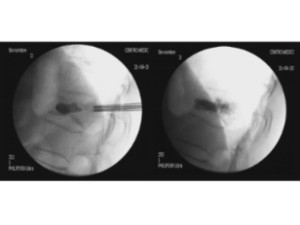

Comparació pre- i post-operatoria d’una cifopastia cementada

Dona, edat 55 anys, fractura aixafament dret de L2

Abans 1

Després 1